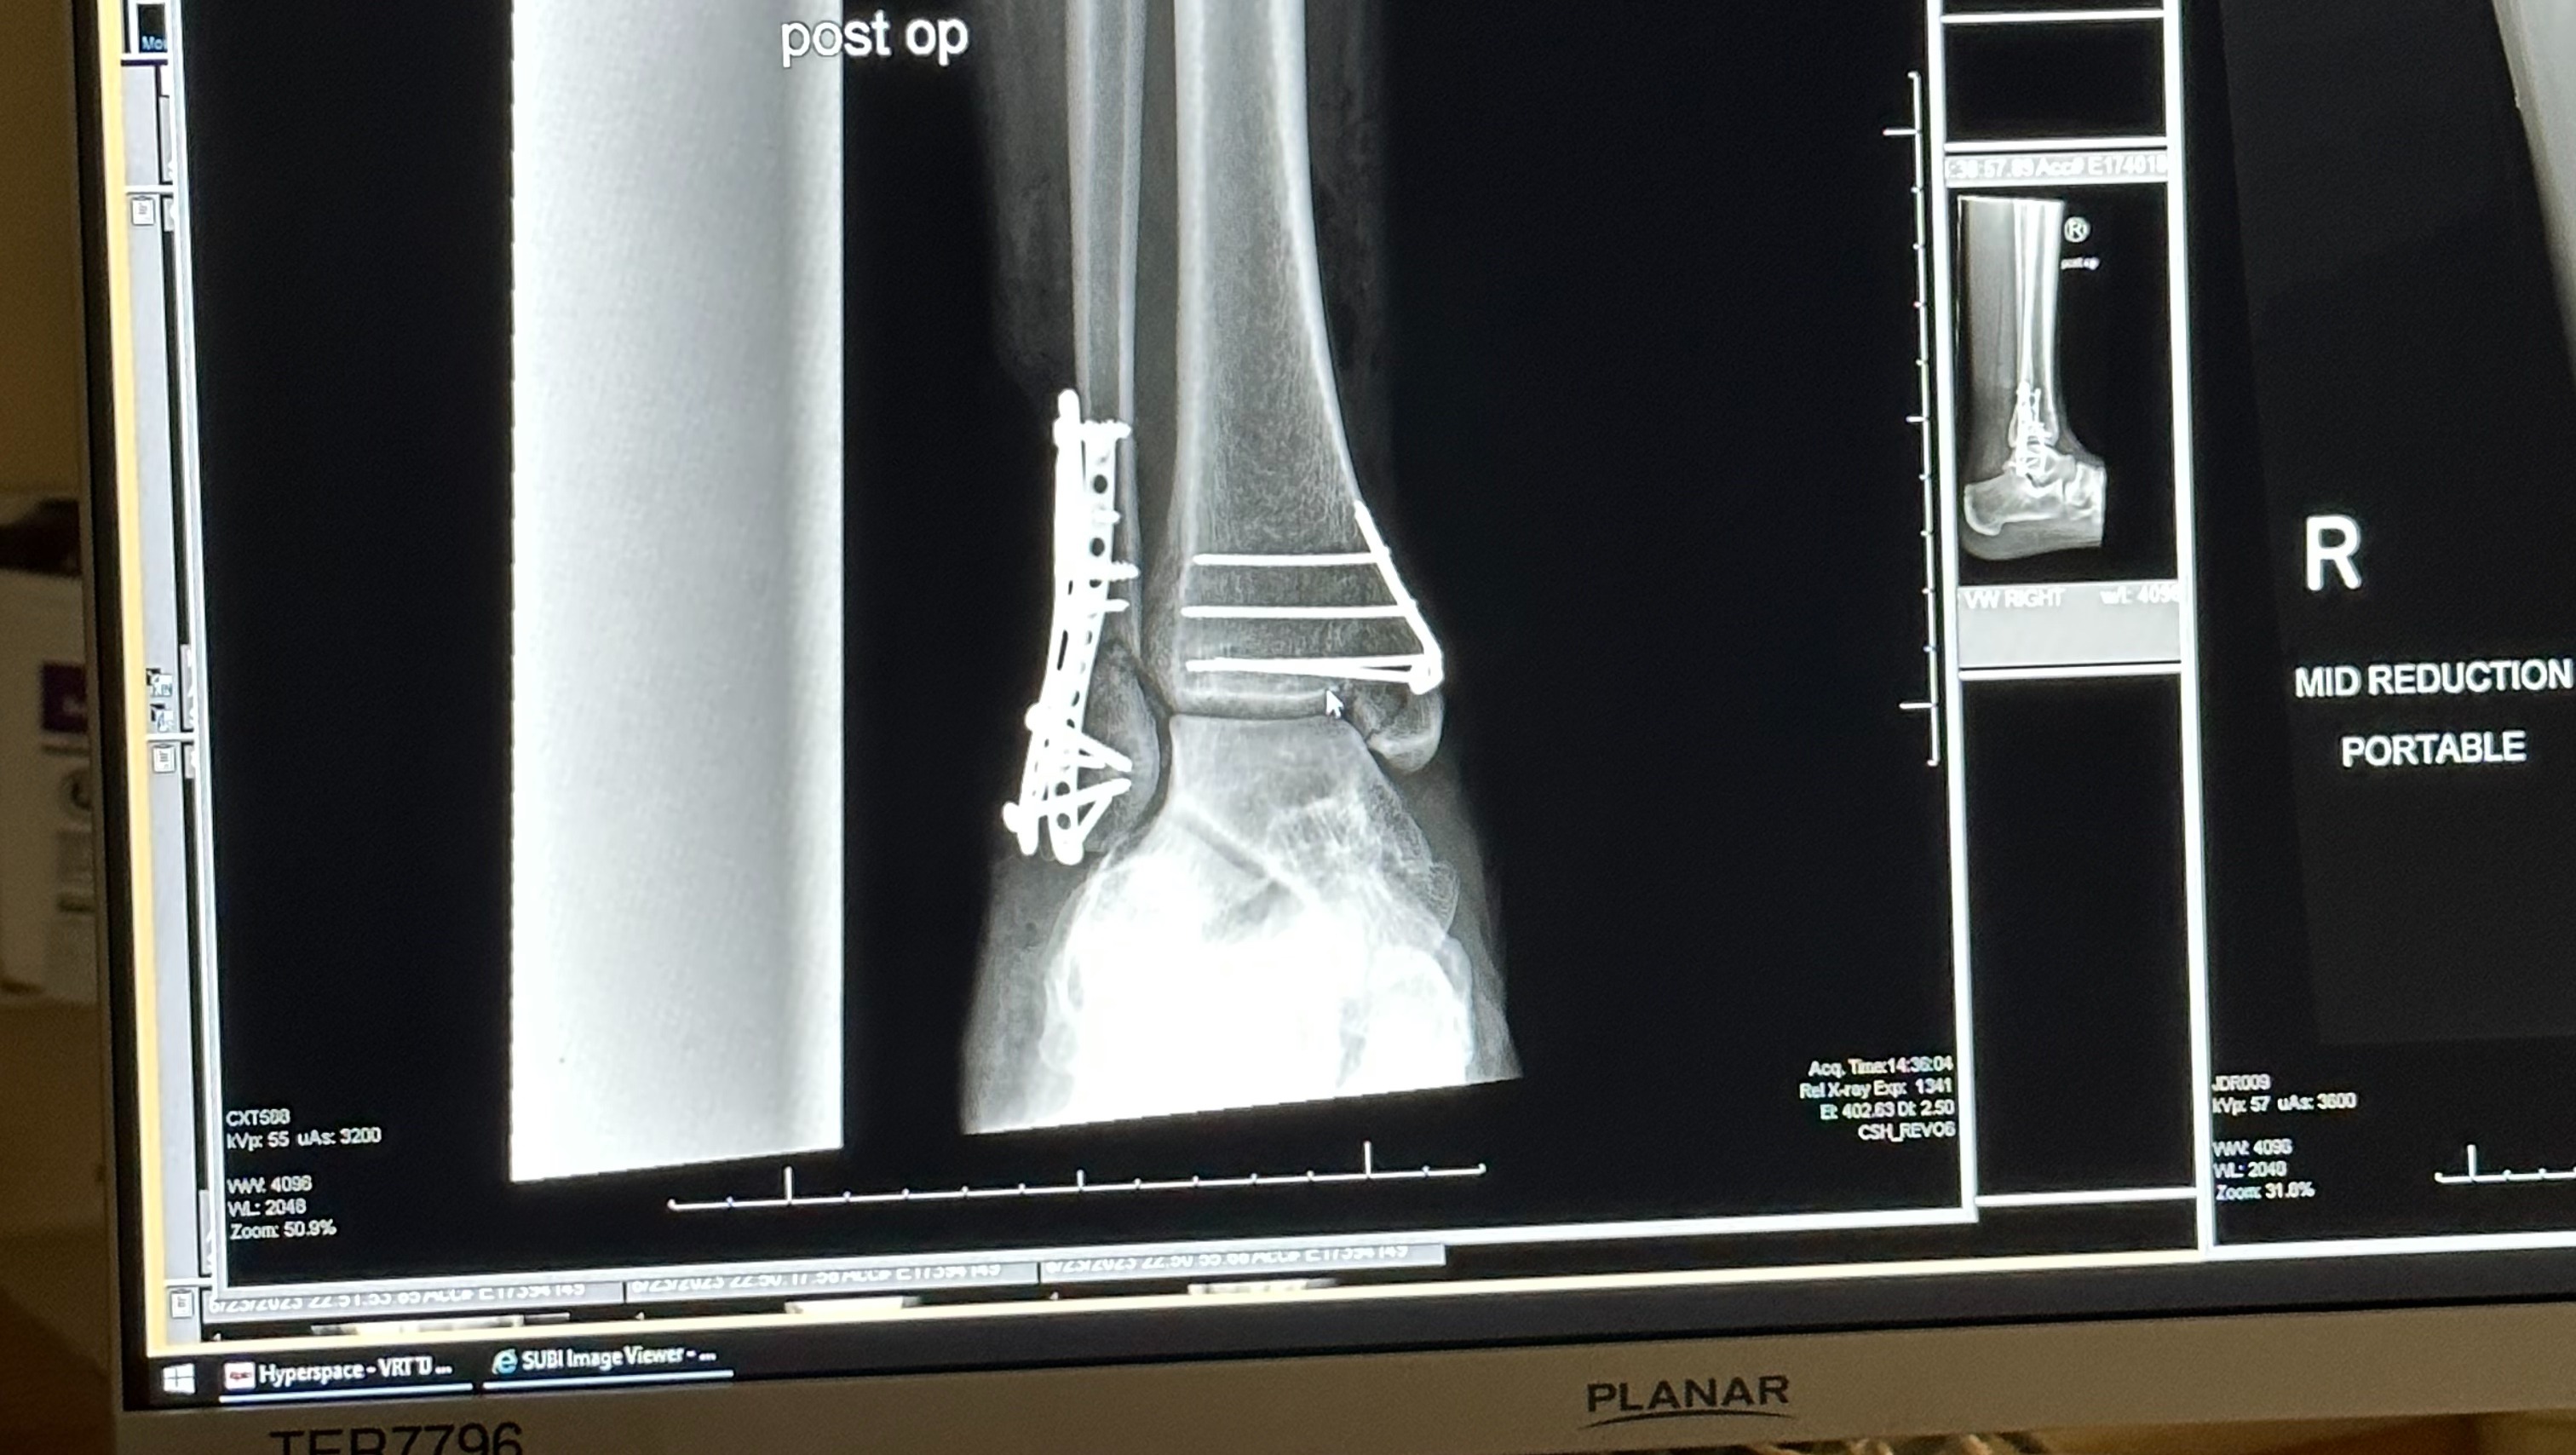

On August 23rd, Luis was severely injured in a hit-and-run. He was struck by a car on 676 that did not stop after they hit him. The accident inflicted serious injuries and wounds to his lower legs. He broke his tibia and ankle, injured his knee, endured major wounds and more. We're thankful for the passersby who stopped on the highway, the state troopers who wrapped his legs, the EMTs and the incredible staff at Jefferson Hospital in Philly for saving his life, and his legs.